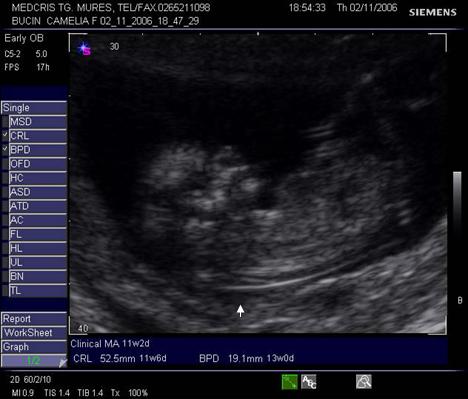

marimea embrionului/fatului (crown rump length = CRL = lungimea craniocaudala, BPD = diametrul biparietal = Biparietal diameter)

Fig. nr. 28.

Sectiune transversala prin craniul fetal, la 12 sapt se remarca simetria

plexurilor choroide, viitoare emisfere cerebrale